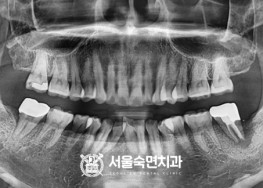

임플란트-치료-전후사진

서울대학교-출신-보건복지부-인증-통합치의학과-전문의-2인-책임관리